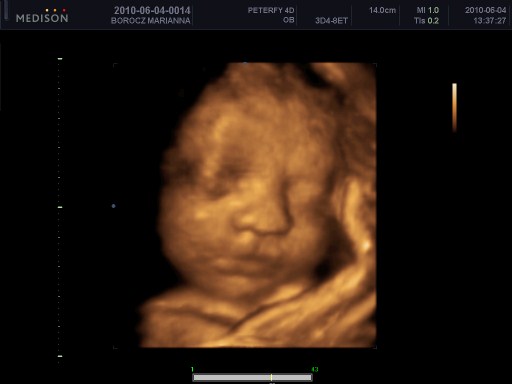

)) és mondja, hogy ő itt semmilyen hematómát nem lát... Itt az egyik gyönyörű petezsák, ott meg a másik.

Mondom.... MÁSIK? MÁrmint IKREK?

MIre ő: IGEN. Nem tudták?

Még nem volt szívhang, de mondta, SZ, hogy korán is hívtak vissza, már csak 6+0 napos vagyok, szóval, ilyenkor még normál bébinél sem mindig van. Viszont az ikrek picit lassabbak, így jövő héten már biztos lesz!

Amit elfelejtettem megkérdezni, hogy mennyire kell vigyázni most magamra... Valakinek ötlet? Ikreseink? Elvileg nincs semmilyen hematóma, minden szuper, az egyik petezsák 8, a másik 10 mm. A nagyobb szép hosszúkás, nem kerek. De ez mindegy.